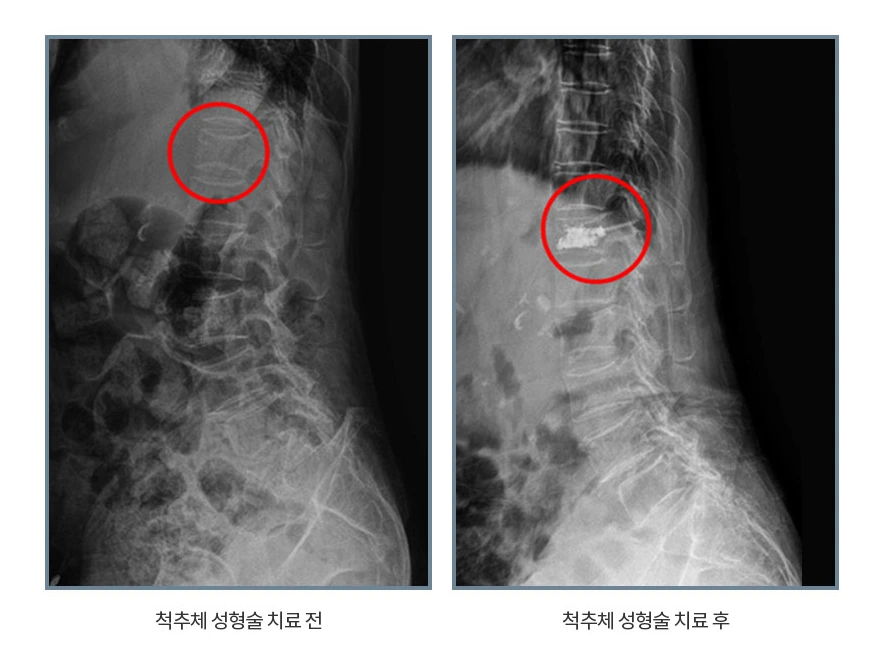

비수술적치료인 경피적 척추체성형술로 치료

전 의료진이 허리 스포츠 메이져 대학병원 전임의 출신인 에이스병원에서는 척추압박골절 치료로 경피적 척추체성형술이 시행됩니다. 과거에는 나사못을 이용해 고정하는 수술을 시행했으나 최근에는 피부 국소마취만 시행한 후에 X-선 투시기를 보면서 골절된 척추체에 골 시멘트(RMMA BONE CEMENT)를 주입하는 경피적 척추체성형술을 실시하지요.

척추압박골절.PNG

조현진 원장님“골절로 인해 척추뼈가 심하게 주저 얹거나 통증이 나아지지 않으면 골절된 척추체에 주사바늘을 이용해 골시멘트를 주입하는 수술인 경피적 척추체성형술은 척추뼈의 높이를 회복시켜 통증을 빠르게 감소시켜준답니다. 특히 전신마취가 아닌 국소마취로 노인환자가 골절로 거동을 못하여 생기는 심폐기능의 합병증으로 인한 사망 가능성을 낮출 수 있습니다”라고 경피적 척추체성형술을 상세히 설명해 주시며 다만 신경이 눌려서 손상이 된 경우에는 수술적 치료를 고려해야 한다고 덧붙이시네요.